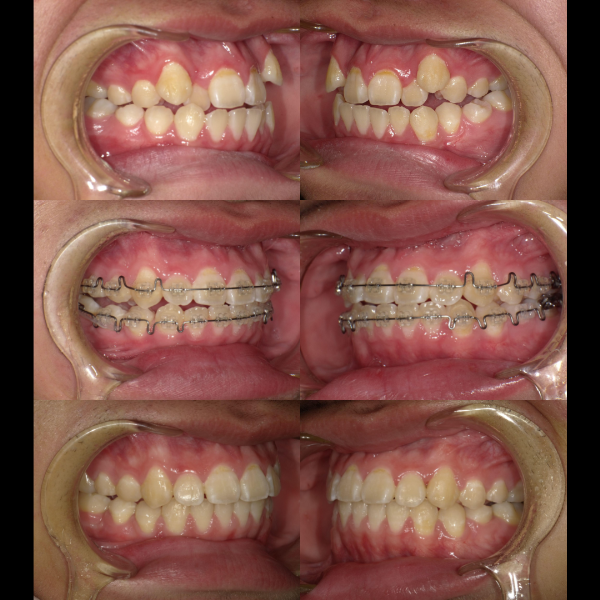

現在、歯列不正になる原因は、下顎の位置関係、歯の傾きなど様々な要因があることがわかっています。

そういった様々な要因を取り除くことで、従来、小臼歯(4番、5番)を抜歯しなければ治療できない症例でも、非抜歯で治療可能となってきているのです。

機能的に小臼歯は非常に大切な歯であることから、最大限小臼歯を抜歯せずに治療できる治療方針を考えます。

また、下顎の位置関係、歯の傾きなどの原因を新素材ゴムメタルワイヤーで治療を行うことでほとんどの症例で小臼歯を抜歯しなくても治療可能になってきています。